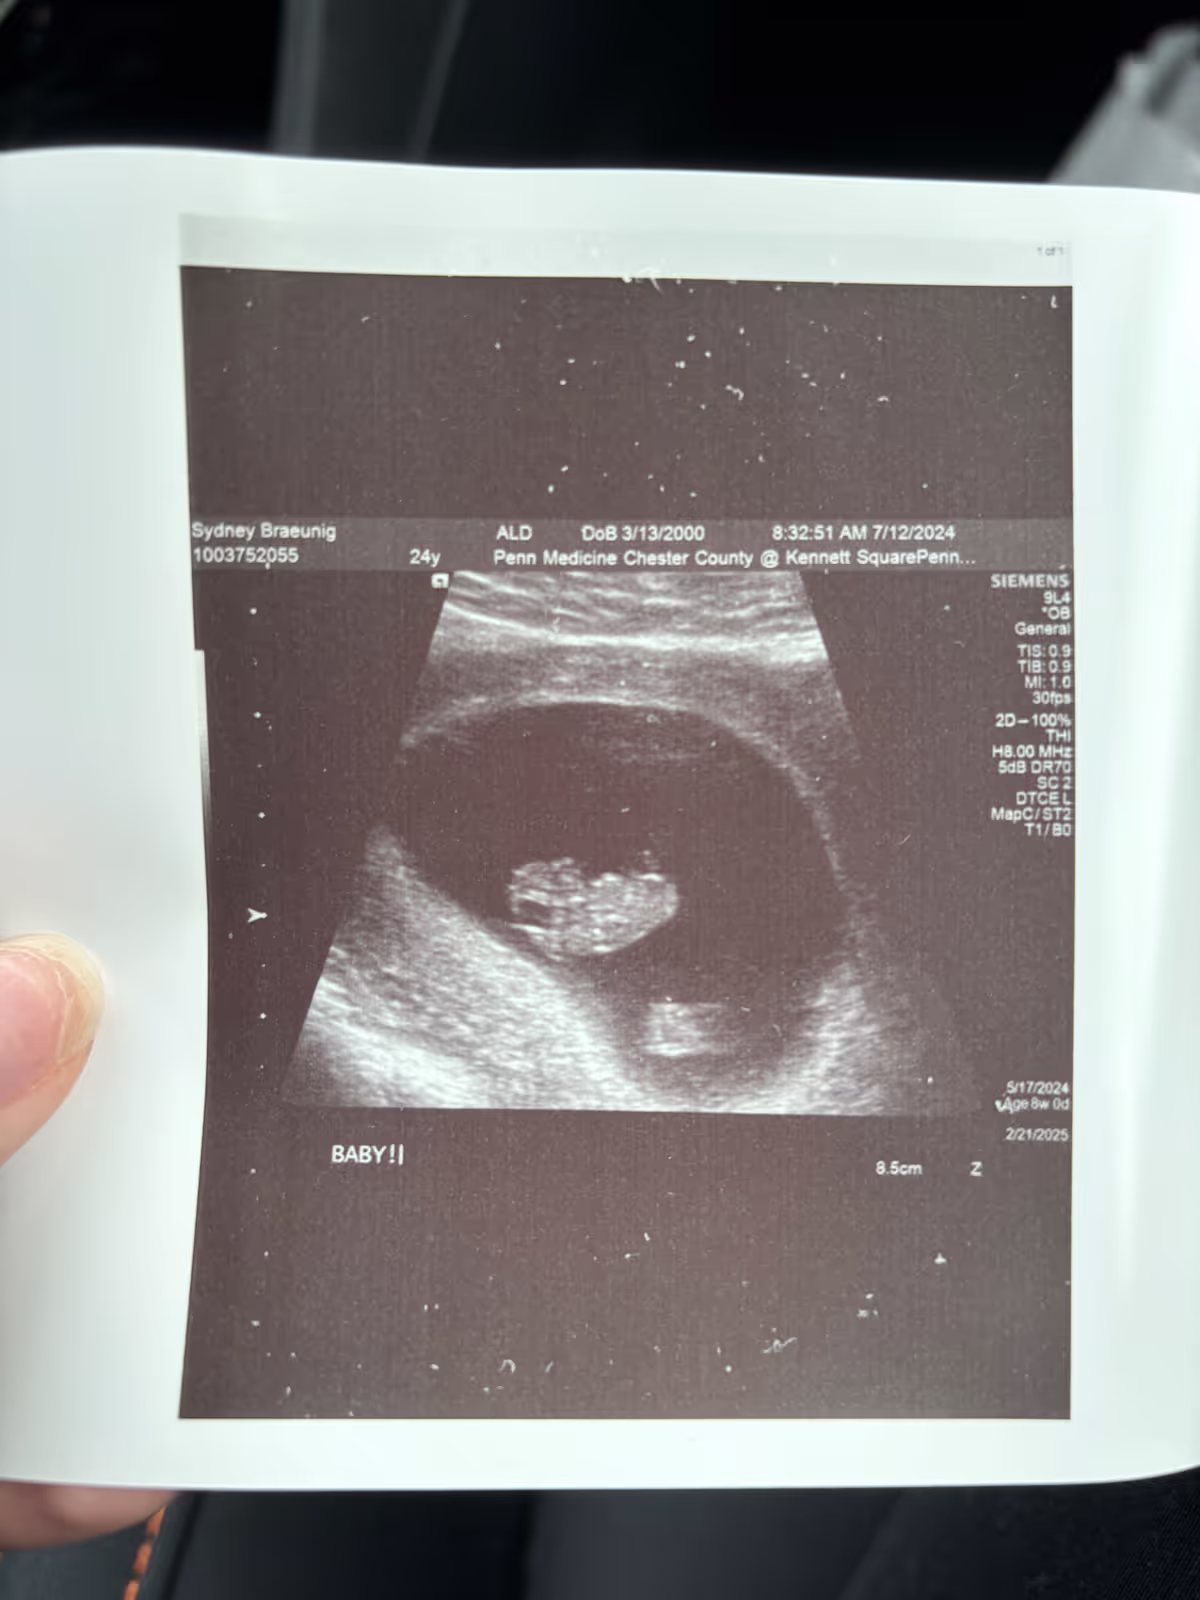

To say this was a crazy, stressful week would be an understatement. Aside from working 36 hours, which kept my tinkering time to a minimum, we're dealing with a medical challenge. I found out back in June that I'd be a grandfather for the first time. My step-daughter Sydney is due in late February early March. Only nobody told the baby.

Sydney's been in the hospital since Monday with bad contractions. With the baby only around 31 or so weeks, it's obviously early. So the hospital is monitoring both mother and daughter in a room next door to the NIC unit. Everyone is trying to hold off on the delivery but Sydney will be in the hospital until she delivers. That could be in hours, days or weeks.